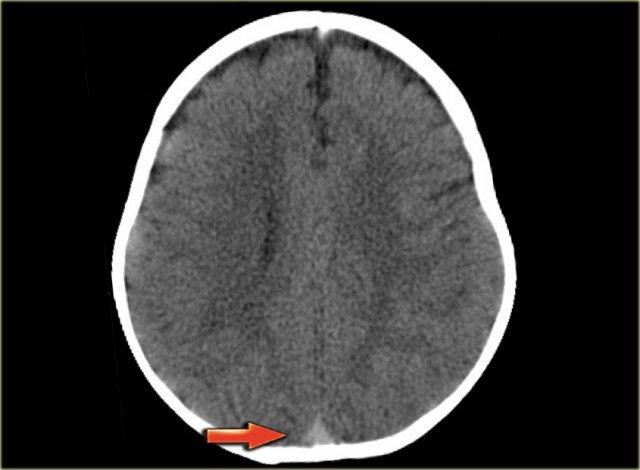

Nhồi máu tĩnh mạch (2) – Huyết khối xoang tĩnh mạch dọc trên

Cấu trúc tĩnh mạch bị huyết khối thường gặp nhất là xoang tĩnh mạch dọc trên.

Nhồi máu gặp trong 75% các trường hợp.

Các bất thường có vị trí cạnh đường giữa và thường có tính chất hai bên.

Xuất huyết gặp trong 60% các trường hợp.

Hình ảnh bên trái cho thấy phù nề cạnh đường giữa hai bên và xuất huyết nhỏ ở bệnh nhân huyết khối xoang tĩnh mạch dọc trên.

Hình ảnh bên trái là tái tạo CT mặt phẳng đứng dọc của một bệnh nhân có xuất huyết cạnh đường giữa hai bên do huyết khối xoang tĩnh mạch dọc trên.

Mũi tên đỏ trên hình CT có tiêm thuốc cản quang chỉ khuyết thuốc do huyết khối gây ra.